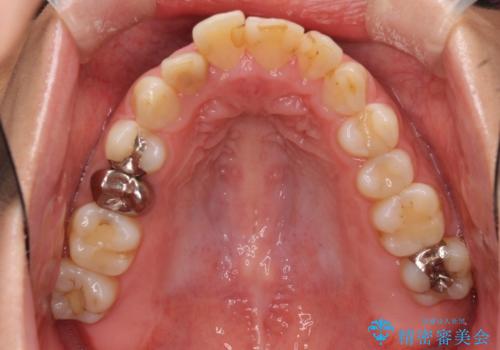

口元の突出感はあまり気になっていませんでしたが、上下の前歯の前後差が大きかったため、上顎左右の第一小臼歯を抜歯し、上顎が裏側装置であるハーフリンガルにて矯正治療を行うこととしました。

矯正治療後は、気になっていた銀歯を全てセラミックとし、きれいな口元に仕上げることができました。